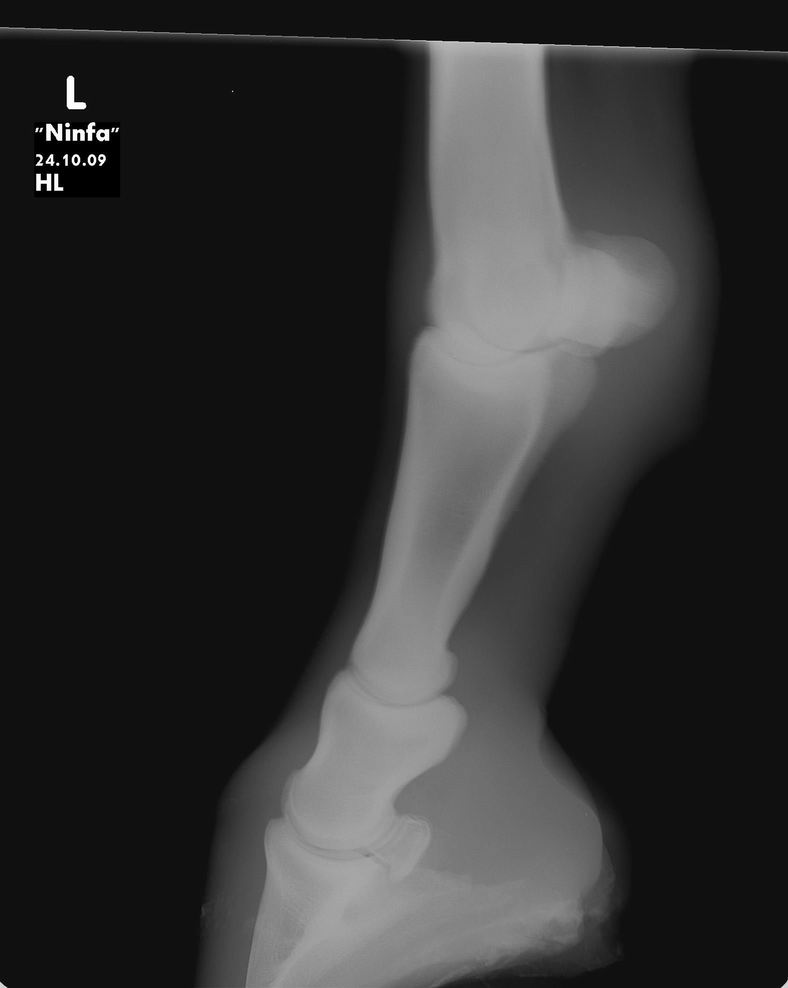

Posted on Monday, Nov 16, 2009 - 4:55 pm: Dear Dr O,I can give you for now some radiographs of the mare. She is not on bute, she is not a riding horse, just on the pasture. For the moment she is walking better after my last trim (left the complete heel) Next week I can give you more exterior pictures of the mare. Tom ![]() ![]() ![]()

Posted on Tuesday, Nov 17, 2009 - 7:09 am: Hello cavalonatural,I am trying to figure out what questions you have about these radiographs. Though I do not do radiographic interpretations from standard resolution internet images there is not much to say about these other than they are incomplete studies of the regions studied. There is not enough of the hoof to really help us though there is an impression of adequate sole, but I can't be certain since the bottoms are cut off. Concerning whether and how to shoe, when we can see the hooves and how well balanced they appear I think we will be able to help more. Be sure the images are taken with the horse standing square. DrO |